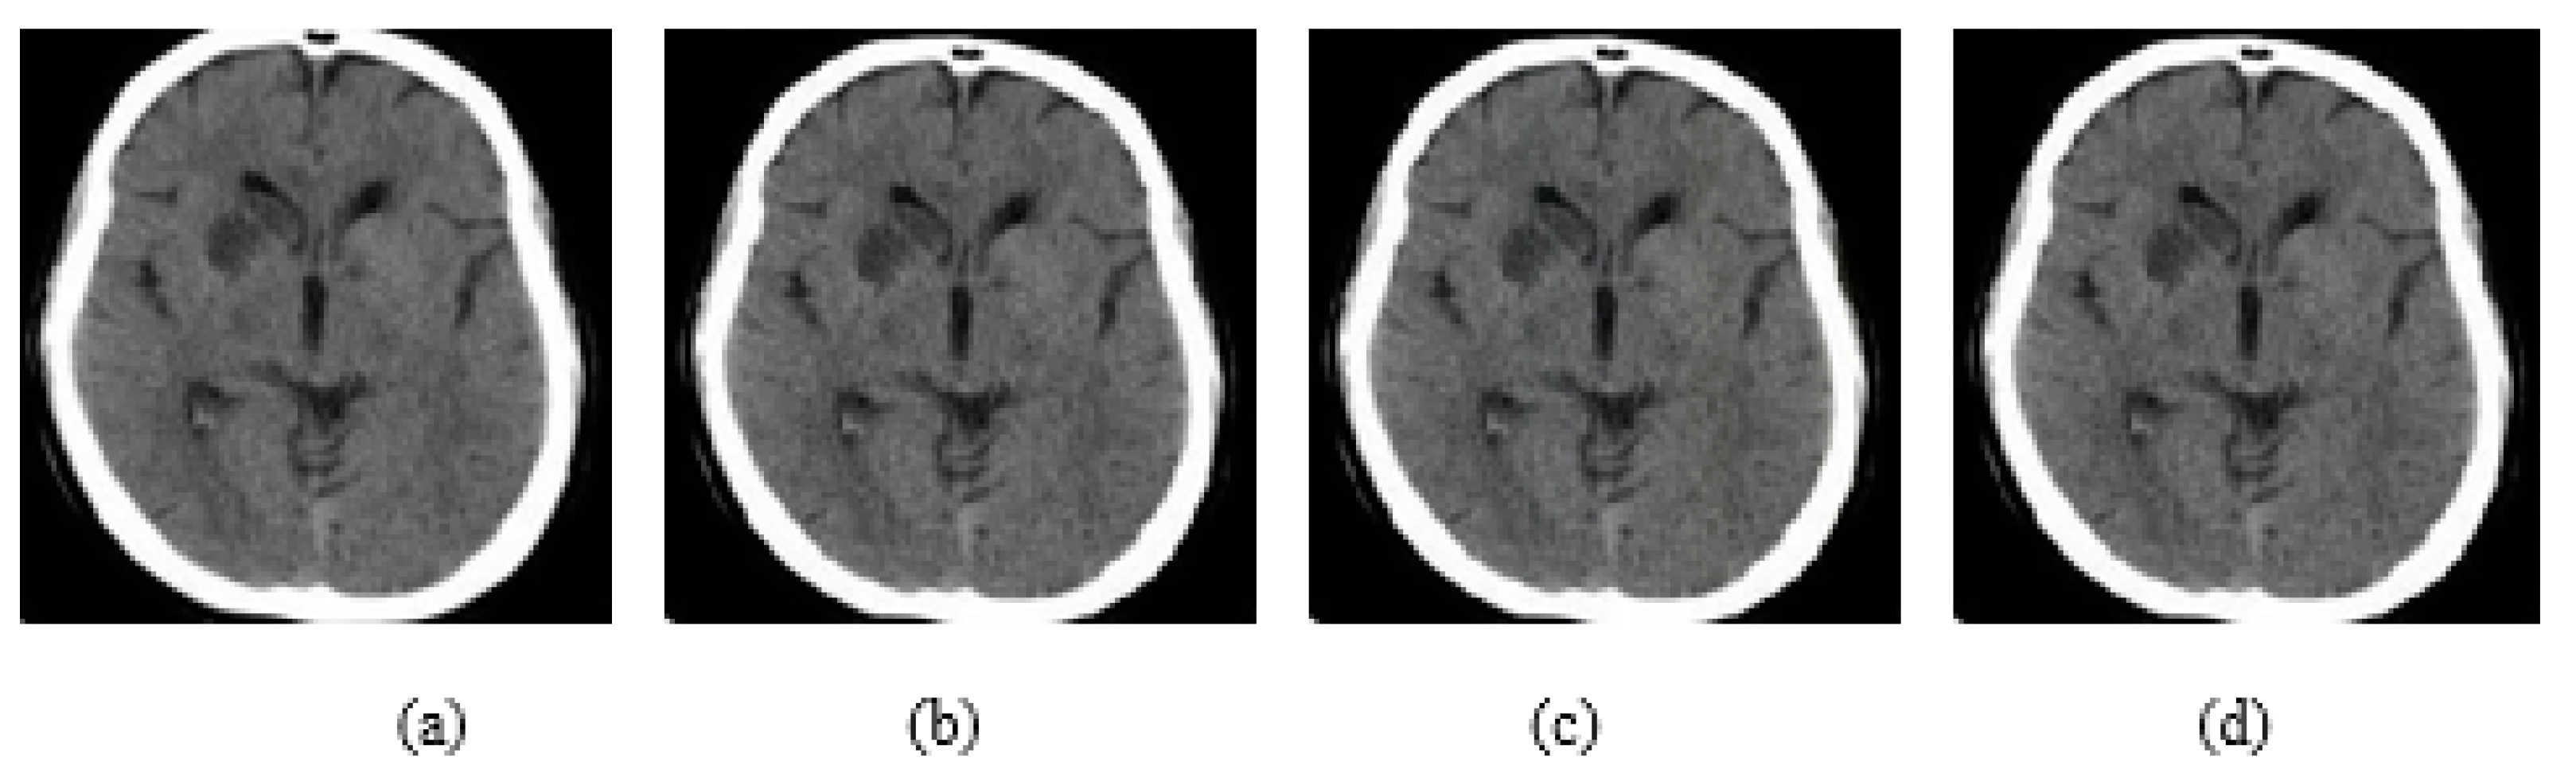

4.1. Datasets

4.2. Ablation Study

4.3. Results